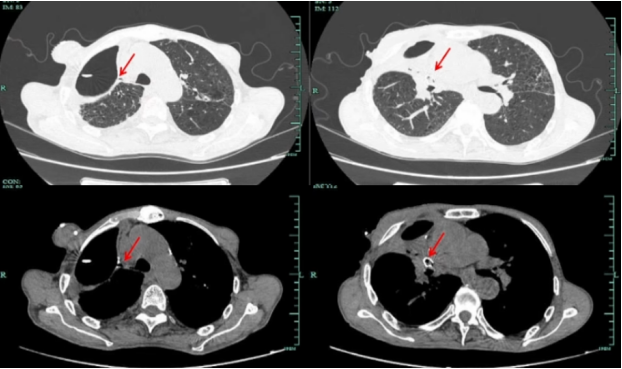

既往有右肺恶性肿瘤手术史15年前,病理类型为低分化非小细胞肺癌,肿块大小4.2 cm×3.3 cm,免疫组化:CEA部分+P53+),Ki-67 45%+TTF-1+EGFR-NSE-,不定期复查胸部CT2018年6月12日胸部CT:右上肺残腔以及少量积液1

图片

1  患者既往胸部CT(2018-06-12)